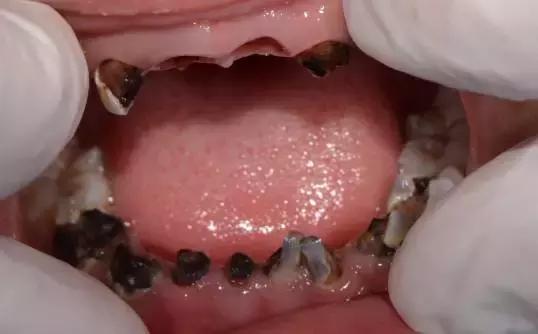

某牙医在博客发布了个史上最恐怖案例:男孩5岁,爷爷奶奶带,1岁起每天3瓶可乐,每天睡前一大杯牛奶,从来不刷牙。结果是20颗牙,8颗烂得只剩牙根,6颗齐根折断,不仅吃饭成了难题,现在就连话都说不清。

下图高能,怕不舒服请别看

稍微好点的案例有,不过恐怖指数也很高了。。。